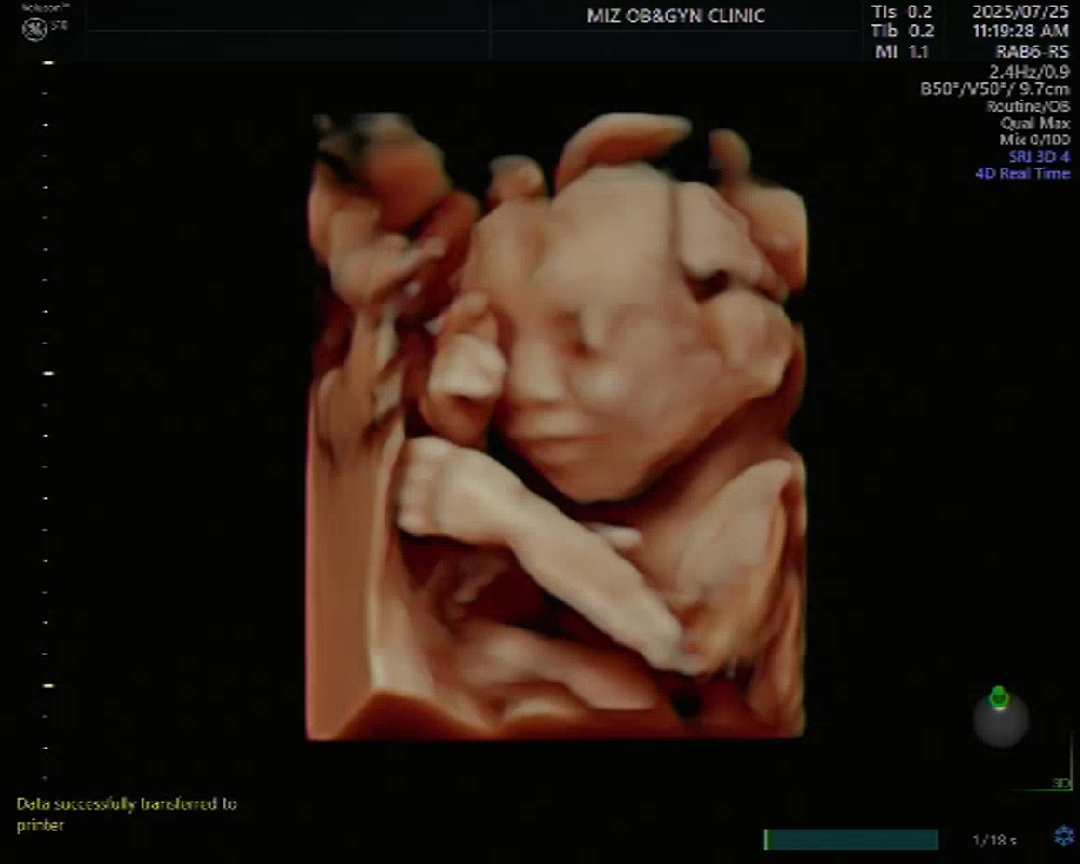

20주 아기 입초사진

20주 3일, 정밀 초음파 진료 후에 원장님께서 입체 초음파 사진을 찍어주셨어요. 둘째인데도 초음파 볼 때마다 신기하고 새로워요. ㅎㅎ 웃을 듯 말듯한 아기 모습 보고 가세요♡ 날씨는 덥지만 오늘도 파이팅!!